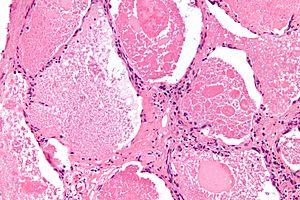

Intermediate magnification micrograph of pulmonary alveolar proteinosis. H&E stain.

The diagnosis of PAP is made using a combination of a person's symptoms, chest imaging, and microscopic evaluation of lung washing/tissue. Additional testing for serum anti-GM-CSF antibodies are helpful for confirmation.[10]

Although both the symptoms and imaging findings are stereotypical and well-described, they are non-specific and indistinguishable from many other conditions. For example, chest x-ray may show alveolar opacities, and a CT may show a crazy paving lung pattern, both of which are seen more commonly in numerous other conditions.[11] Thus, the diagnosis primarily depends on the pathology findings.

Lung washings or tissue for histopathologic analysis are most commonly obtained using bronchoalveolar lavage and/or lung biopsy.[12] Characteristic biopsy findings show filling of the alveoli (and sometimes terminal bronchioles) with an amorphous eosinophilic material, which stains strongly positive on PAS stain and the PAS diastase stain. The surrounding alveoli and pulmonary interstitium remain relatively normal.[13] Electron microscopy of the sample, although not typically performed due to impracticality, shows lamellated bodies representing surfactant.[14] An alternative diagnosis with similar histomorphologic findings is Pneumocystis jirovicii pneumonia.[14]

Lung washings characteristically yield a fluid which is "milky"composition. Under the microscope, samples show 20-50 micrometer PAS-positive globules on a background of finely granular or amorphous PAS-positive material. There is typically a low numbers of macrophages and inflammatory cells (although this is variable).[13][14]